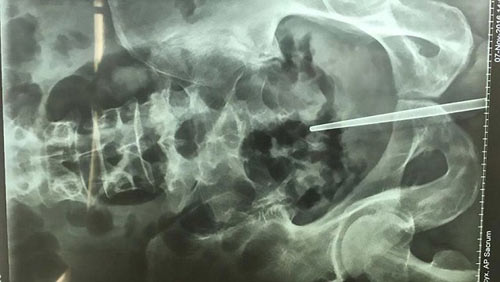

Kết quả chụp chiếu cho thấy chiếc đũa đã chạm tới thành trực tràng của anh Chen

Anh Chen nhanh chóng được đưa tới bệnh viện cấp cứu. Kết quả chụp chiếu cho thấy chiếc đũa đã gần chạm tới trực tràng của anh Chen và đang gây nguy hiểm cho sức khỏe nếu nó làm thủng trực tràng.